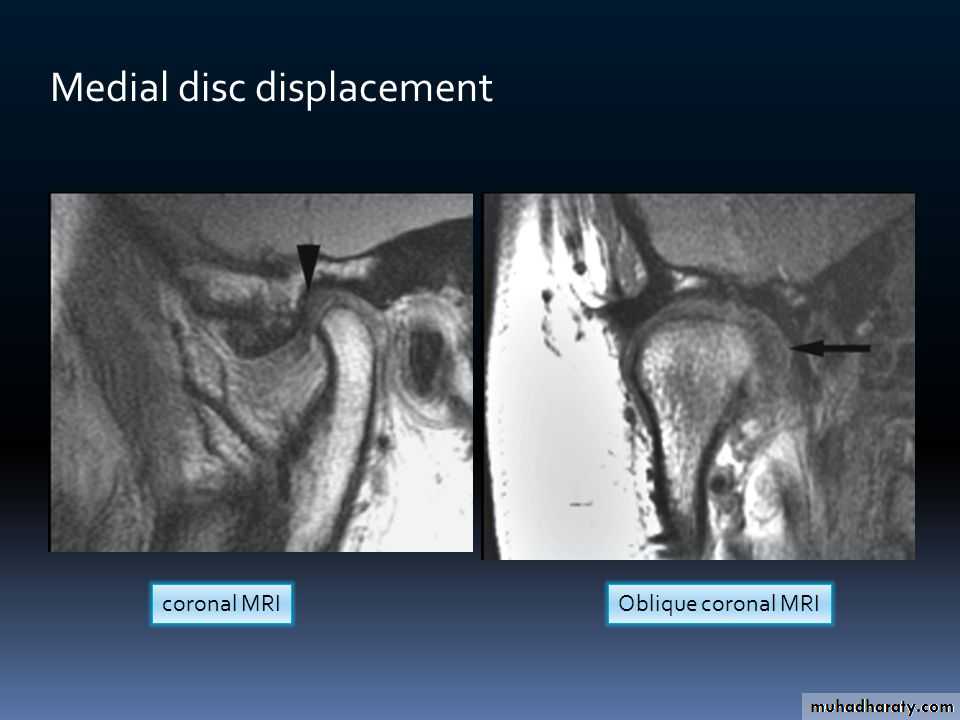

provides evaluation of a variety of hard and soft tissue pathology in the joint which can be done from a single radiation exposure. + CT images provide the most accurate radiographic assessment of the bony components of the joint• magnetic resonance imaging:

• which is most effective diagnostic imaging technique to evaluate TMJ soft tissue (intra-articular soft tissue) and for disk morphology and position with the fact that this technique does not use ionizing radiation is a significant advantagesDiseases of TMJ :A. traumatic arthritis:

• in this case movement of the condylar head is restricted and the damaged meniscus used to be blamed as the cause of the painful and locking joint. if the disk lies behind the condyle so it cannot return to its proper position in the glenoid fossa.